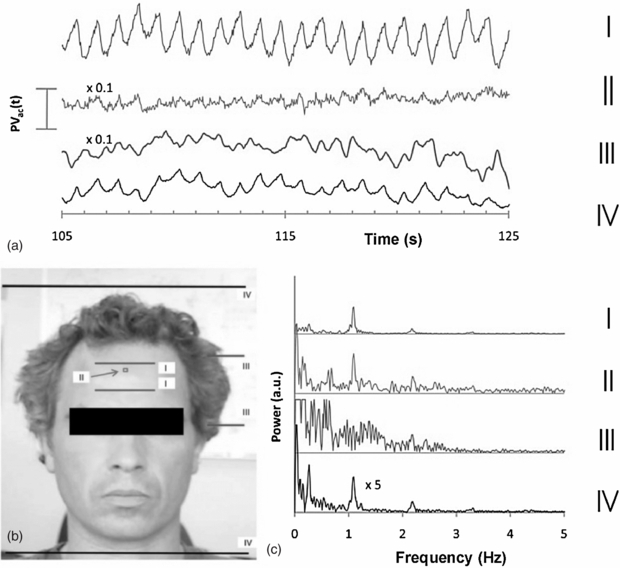

Photoplethysmography imaging (iPPG) is a non-contact imaging method for mapping cardiac synchronous pulsations i.e. perfusion across an area of tissue. iPPG has various forms and can be single wavelength field illumination (near infrared) or dual wavelength illumination (both red and near infrared). iPPG can also be used to determine oxygen saturation by employing algorithms and empirical formulae similar to that of traditional single site contact pulse oximetry. iPPG mapping of pulsatility represents the regional perfusion for the superficial blood vessels including the microcirculation. iPPG has capability for high resolution, fast scanning speeds and can ultimately be of low-cost. The technique can be unreliable where there is significant movement artefact, and correction algorithms are a key part of ongoing technology development. Currently, the literature on iPPG relates to technical advances rather than clinical utility and validity. One very important area with significant commercial potential is its translation to the very low-cost webcam platform. Examples of cardiac synchronous waveforms that can be obtained from the forehead site with iPPG are shown in figure 16.

Figure 16. Cardiac pulsations at different digital camera colours measured from the forehead using iPPG from ambient lighting. Heart rate variability power spectra are also shown (permission granted to re-use from Verkruysse et al 2008 Opt. Express 16 21434–45).